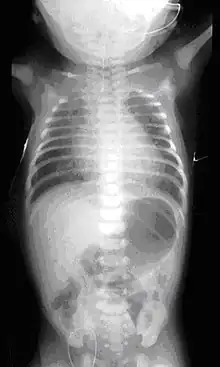

Diagnostic est post-natal

Juste après l'accouchement, deux types de tests peuvent être faits :

- une sonde « naso-gastrique » très fine peut être introduite dans l'œsophage du nouveau-né. Si elle est bloquée après quelques cm, c'est qu'il y a atrésie[3].

- test à la seringue

- l'IRM permet un diagnostic précis, mais est rarement utilisé chez les nouveau-nés[16]

Dans presque tous les cas une anomalie de la trachée est associée, et dans la moitié des cas environ[3], l'atrésie de l'œsophage est associée à d'autres malformations, comme dans le cadre du syndrome de VATER (présent dans 10 % des cas[3]) ou de VACTERL. Il convient donc de rapidement rechercher activement d'autres malformations associées qui peuvent toucher le cœur (dans 30 % des cas), mais aussi le squelette (25 % des cas), les reins, les membres, le système digestif (25 % des cas) ou urinaire[3].... Une échographie et une radiographie de l'abdomen confirme le type d'atrésie et des examens complémentaires portent notamment sur le cœur (échocardiographie) et l'anus (une sonde recherche une éventuelle perforation)[3].